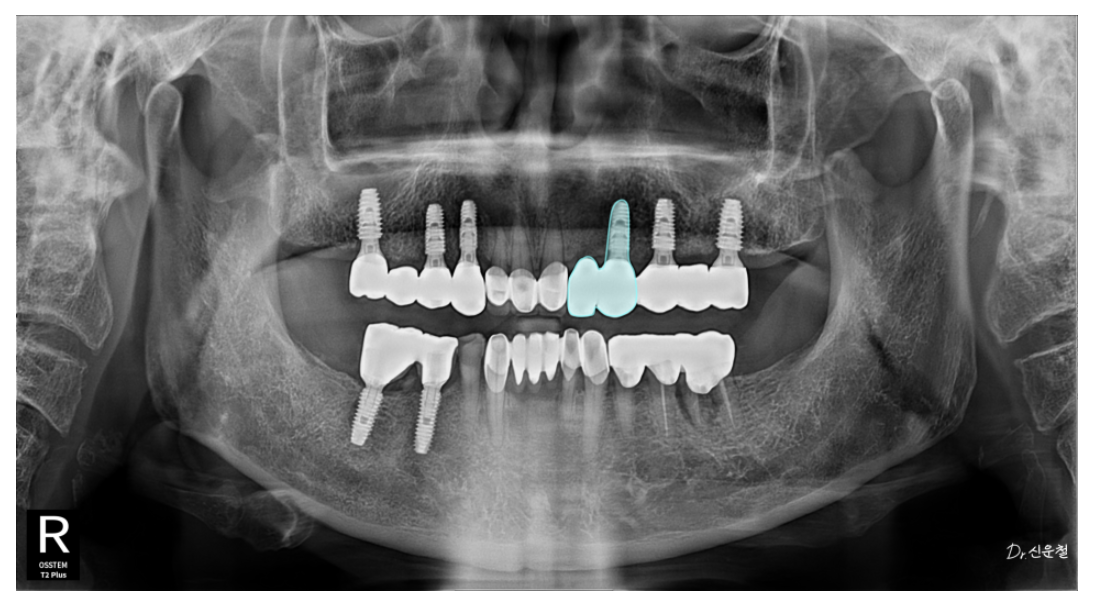

✔ 첫 내원 시 상태 (25.05.01)

앞니 세 개만 남아있는 상태

양쪽 어금니는 모두 상실

오래된 틀니 사용으로 잇몸뼈가 많이 닳아 있음

✔ 앞니 2개가 빠져 있어도 ‘캔틸레버’로 한 개만 심었습니다

앞니는 어금니처럼 강한 힘을 받지 않기 때문에

임플란트 1개로도 2개 역할이 충분합니다.

특히 70대 환자분의 경우,

두 자리 중 한 곳은 뼈가 얇아 수술 부담이 컸기 때문에

더 안정적인 위치에만 임플란트를 심고

옆 치아는 자연스럽게 연결했습니다.

캔틸레버(Cantilever):

한쪽만 기둥이 있고 옆 치아는 떠 있는 형태의 연결 방식.